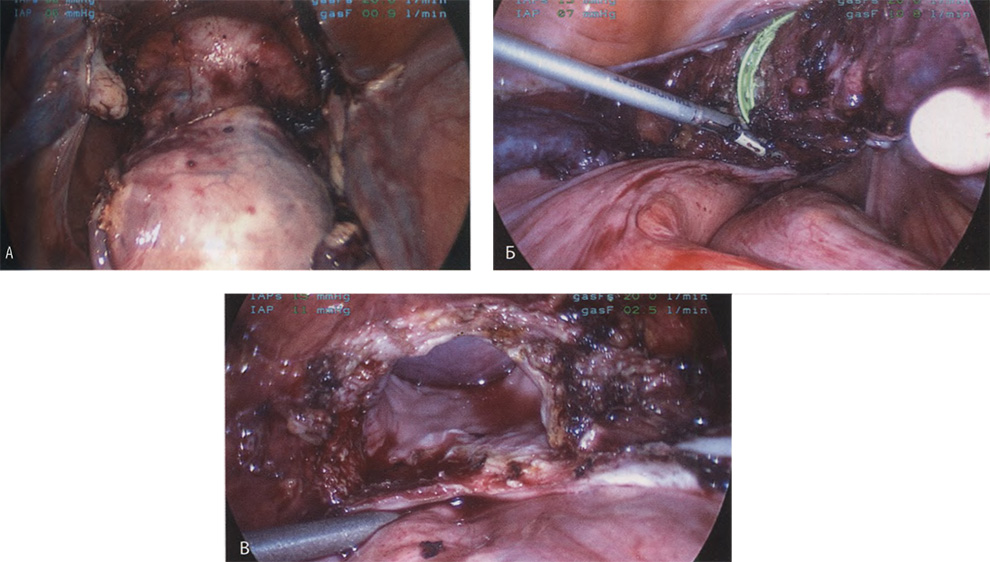

Если оставить в стороне эти достоинства и недостатки, то техника лапароскопической гистерэктомии фактически идентична технике лапаротомической гистерэктомии. В самом начале операции, если она выполняется лапароскопическим методом, необходимо осмотреть всё операционное поле, воспользовавшись для этого панорамным обзором (рис. 12-33—12-37). Операцию начинают с коагуляции и пересечения круглых связок, чем обеспечивается доступ к широкой связке (рис. 12-38—12-40). Брюшину, переходящую с купола мочевого пузыря на переднюю поверхность матки, вскрывают. Пузырь отсепаровывают от матки острым путём (рис. 12-41). После этого вскрывают задний листок широкой связки, а затем принимают решение, оставлять или удалять яичники. Если принято решение оставить яичники, то коагулируют и пересекают собственные связки яичников и маточные трубы (рис. 12-42). Если принято решение удалить яичники (то есть выполнить сальпингоофорэктомию), то с обеих сторон выполняют диссекцию мочеточников от воронко-тазовых связок, которые затем отсепаровывают, коагулируют и пересекают (рис. 12-43). Затем ткань широкой связки отделяют от маточных сосудов (отпрепаровывая их), изолировав, таким образом, мочеточники от маточных сосудов (рис. 12-44 А). Восходящие ветви маточных сосудов коагулируют справа и слева, а затем пересекают (рис. 12-44 Б, В).

Коагулируют и пересекают так называемые поддерживающие связки матки (рис. 12-44 Г, Д). Возможно, потребуется разделить ткани, соединяющие мочевой пузырь с передней стенкой влагалища. После этого вскрывают влагалище и коагулируют все кровоточащие сосуды. Если хирург владеет методами лапароскопического наложения швов, то он зашивает культю влагалища. Предварительно матку извлекают через влагалище или путём морцелляции (рис. 12-45 и 12-46).

Рис. 12-45. А. Матка полностью мобилизована и видна выпуклость на месте введённого во влагалище инструмента. Б. Произведена коагуляция угла влагалища, а само оно частично вскрыто. В. По мере расширения разреза влагалища становится лучше видна влагалищная манжетка.